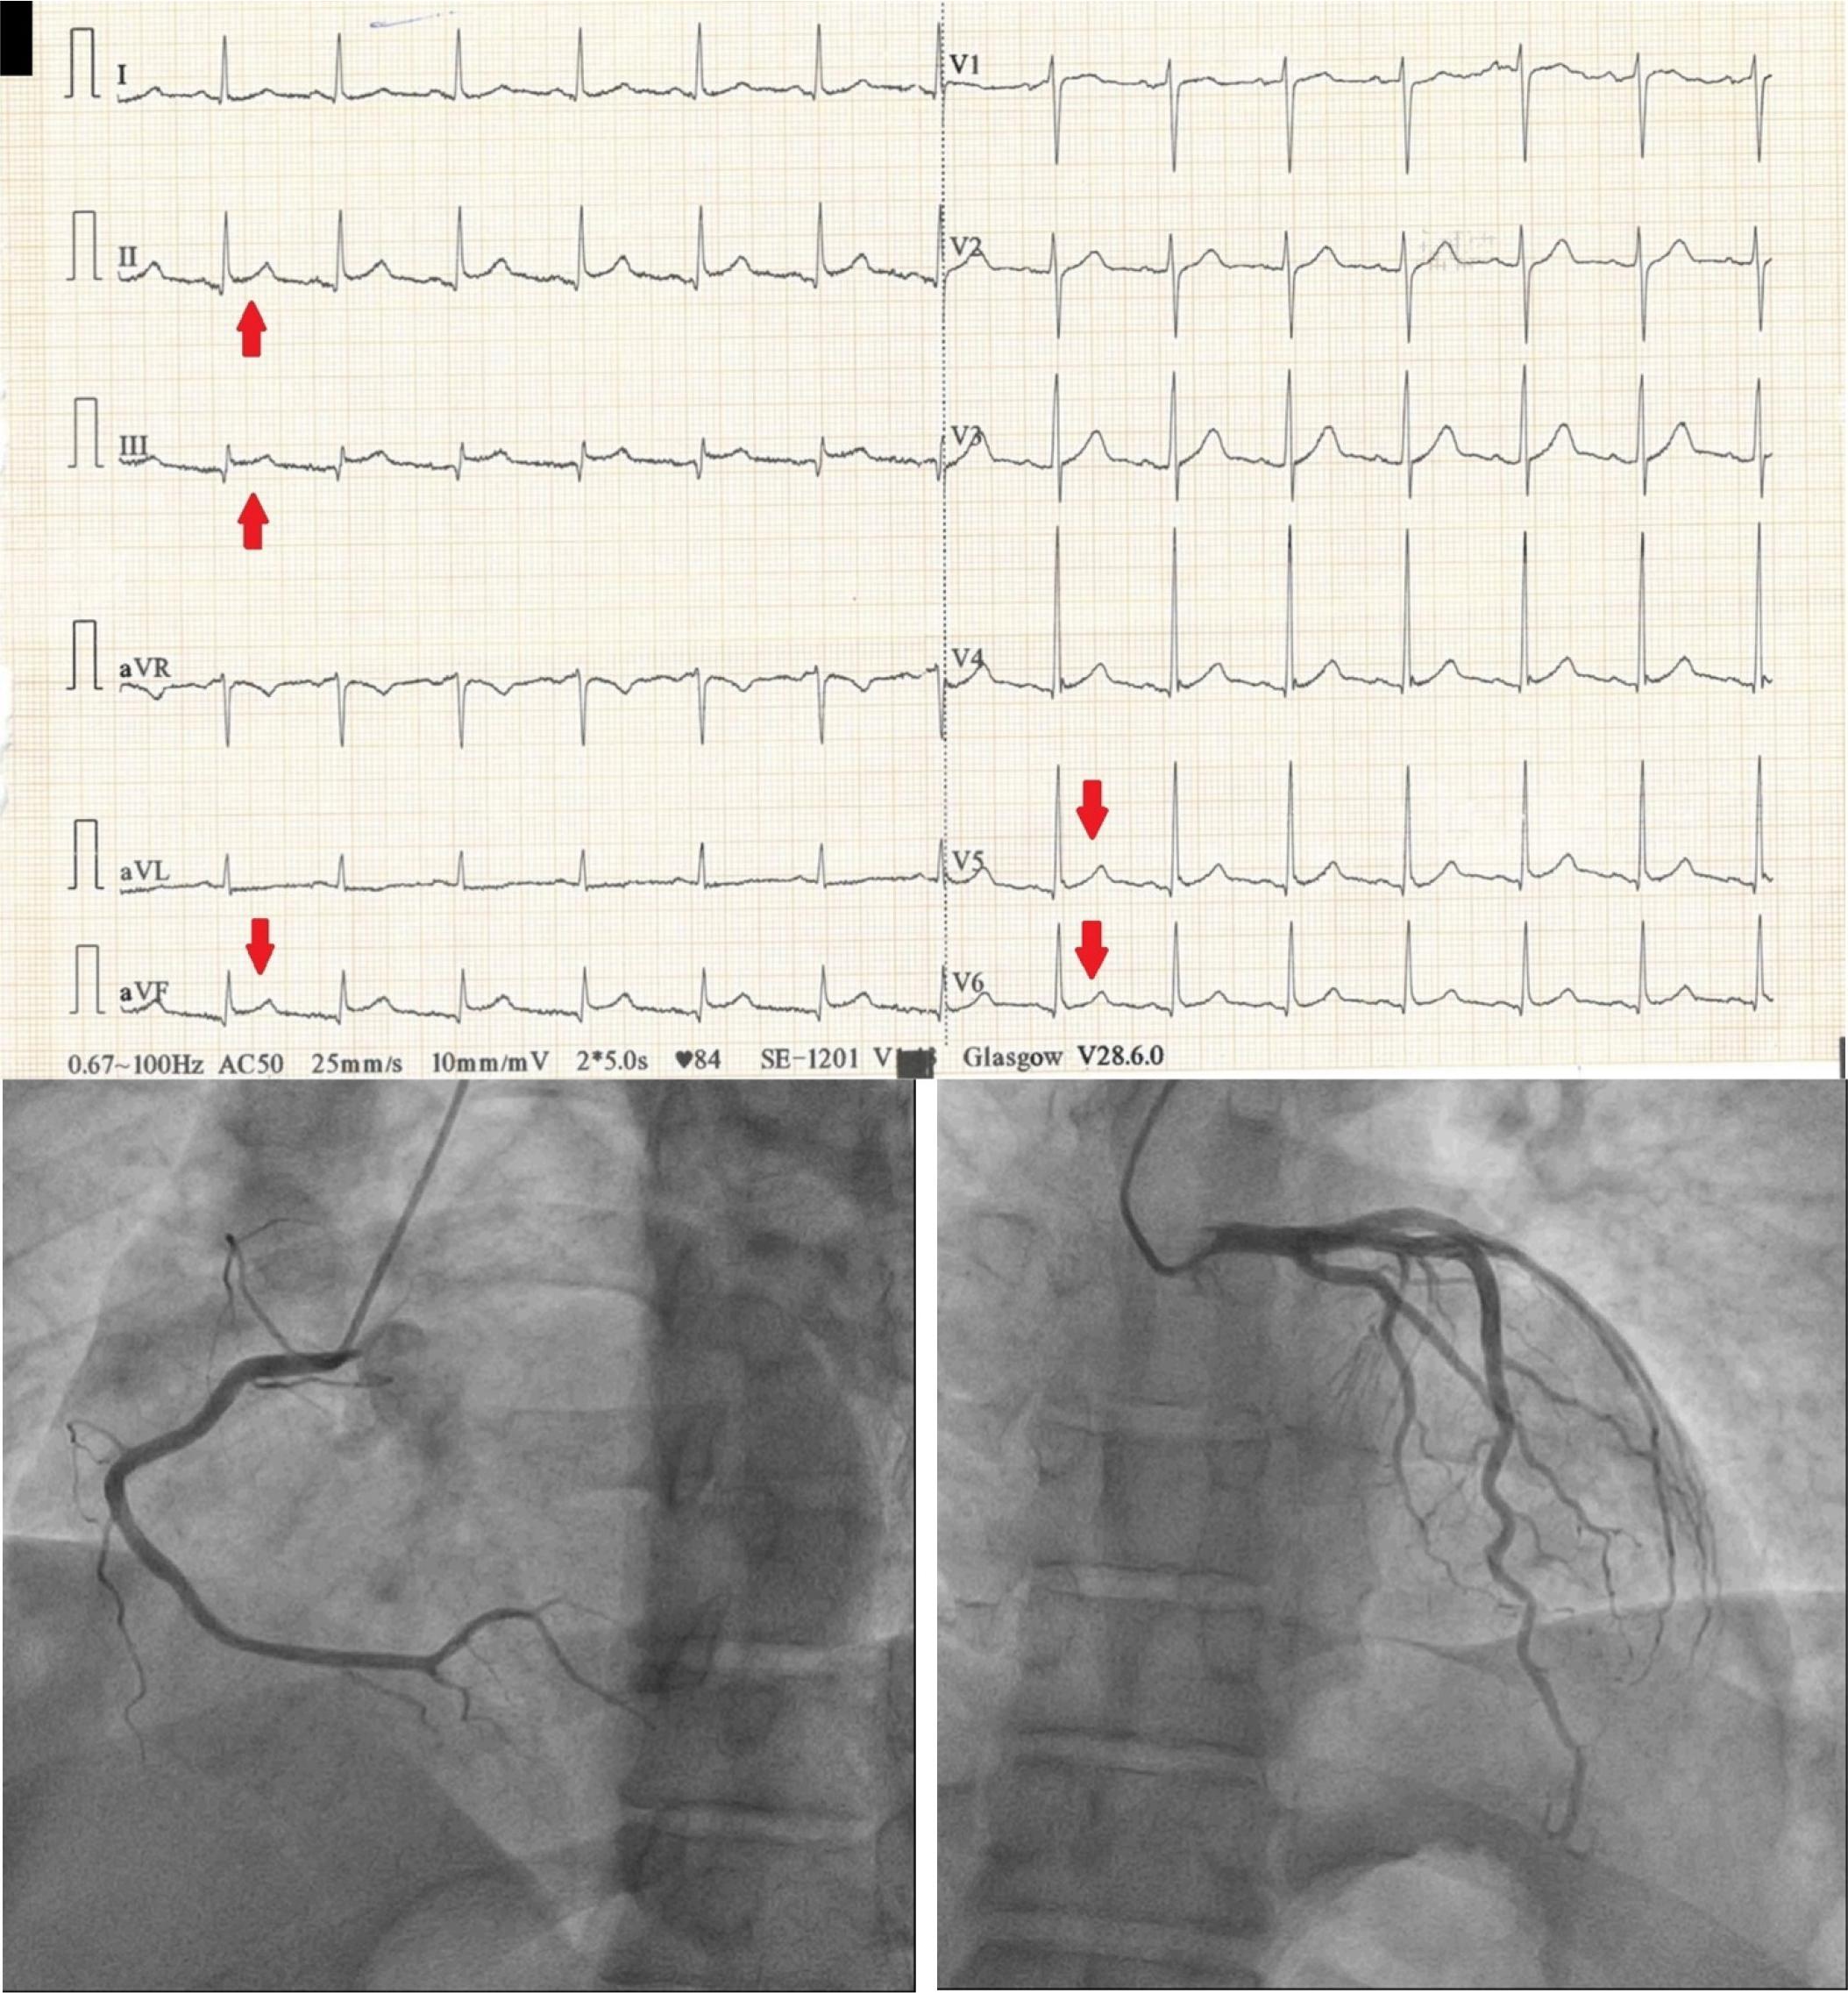

Figure 1